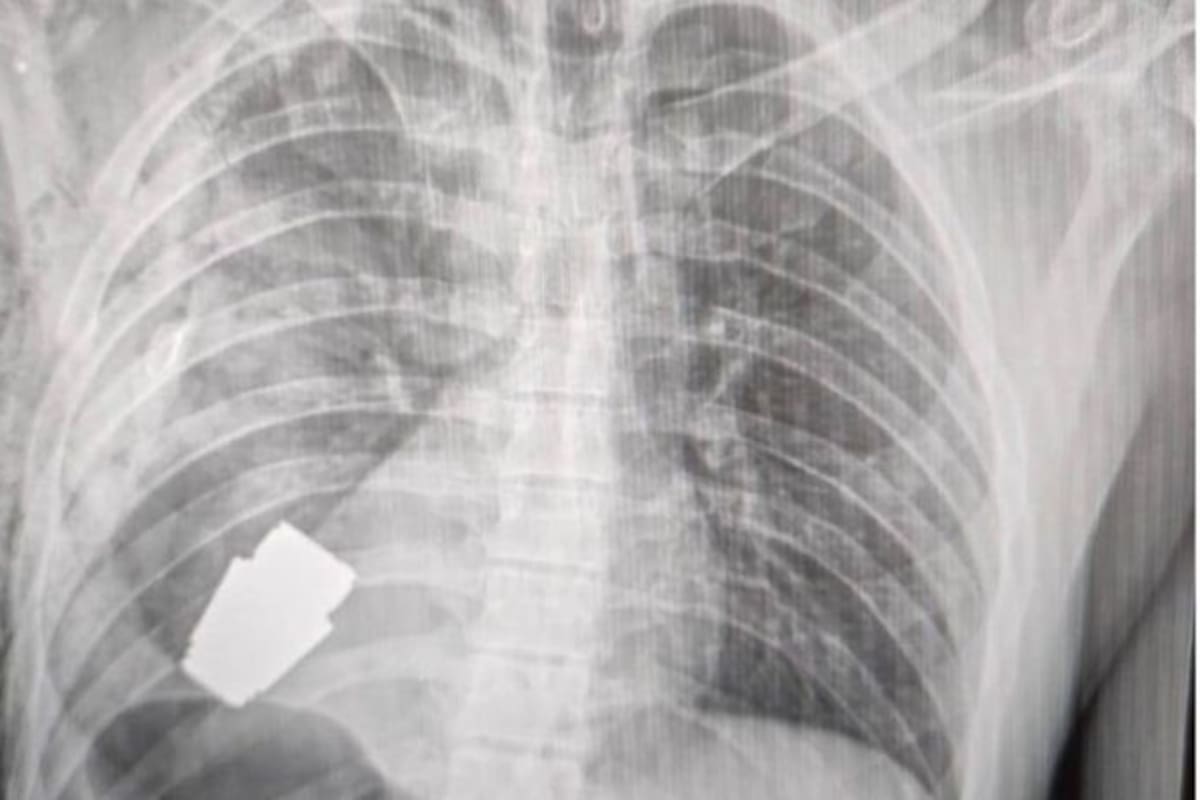

Tic. Tac. El tiempo nunca valió tanto para Andriy Verba, el cirujano militar que, increíblemente, sacó una granada de fabricación rusa que quedó alojada en el pecho de un soldado ucraniano de 28 años.

Se trataba de una granada de cuatro centímetros de diámetro y 275 gramos que, comúnmente, explotan unos 20 segundos después de ser lanzadas.

Agregó que la granada fue extraída bajo la supervisión de dos militares expertos en explosivos para tratar de asegurar la seguridad de los médicos y dar indicaciones para evitar que fuera detonada.

Durante la operación no se pudo utilizar la electrocoagulación, procedimiento común en las cirugías del corazón para evitar que el paciente sufra una hemorragia, por temor a que la corriente eléctrica pudiera detonar la granada.

Lo que más impresiona a los analistas es cómo la granada permaneció sin detonar pese a mantenerse explosiva durante y después de la operación hasta que fue desactivada por los especialistas